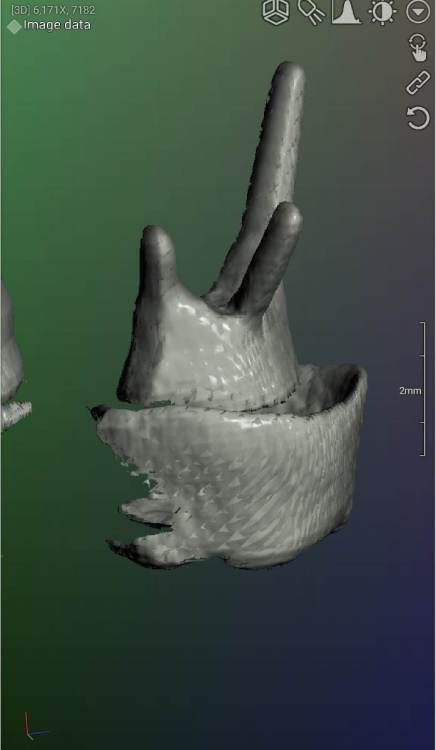

DeLaMer Опубликовано 11 августа, 2021 Поделиться Опубликовано 11 августа, 2021 (изменено) Добрый день уважаемым докторам-участникам форума. Хотелось бы, по возможности, получить экспертное мнение по поводу моей проблемы. На верхней челюсти есть мост, объединяющий 6й, 5й и отсутствующий 4 зубы (если я правильно понимаю нумерацию, это должны быть 24, 25, 26). В начале июня на десне открылся свищ с гноем (абсцесс, но, видимо, не острый, кроме периодического надувания гнойного шарика ничего больше не происходило). По этом поводу мой лечащий врач поднял КТ, которое было сделано осенью до того по другому поводу и обнаружила воспаление одного из корней 6-го зуба. При этом она высказала соображение, что может быть здесь поможет резекция верхушки того самого корня. Один из хирургов, с которым я консультировалась по этому поводу, сказал, что на его взгляд резекция возможна. Другой - что воспаление проявляется не только на одном корне, а на двух и по его мнению сделать тут ничего нельзя, только распиливать коронку и удалять 6й зуб. Я была бы крайне благодарна, если бы уважаемые специалисты высказали свое мнение по этому поводу, потому что при равноценных двух противоположных мнениях мне даже не понятно с чего начинать. Прикрепляю ссылку на файл КТ на своем дропбоксе. Огромное спасибо за помощь https://www.dropbox.com/s/fkv8cvqqq6grgpe/Sergeeva A..zip?dl=0 Изменено 11 августа, 2021 пользователем DeLaMer Ссылка на комментарий

Irouil Опубликовано 12 августа, 2021 Поделиться Опубликовано 12 августа, 2021 По представленным средам создаётся впечатление, что у зуба фактически разрушено соединение между корнями. Риски того, что он под нагрузкой раскроется в любой момент, достаточно высоки Ссылка на комментарий

АнтонТЛТ Опубликовано 13 августа, 2021 Поделиться Опубликовано 13 августа, 2021 (изменено) Там всё ок с фуркацией и вкладка коротконогая. Просто на КТ очень много артефактов. Изменено 13 августа, 2021 пользователем АнтонТЛТ Ссылка на комментарий